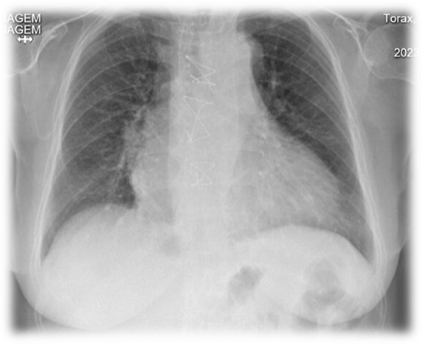

Valvular heart disease is an important cause of morbidity and mortality, with degenerative etiology predominating in developed countries and rheumatic etiology in underdeveloped countries. Aortic valve disease is the most lethal, and echocardiography is the reference test for diagnosis. We will describe the case of an 86-year-old woman with thrombosis of a mechanical aortic prosthesis secondary to a change in therapy from warfarin to rivaroxaban. In view of the patient's age and the risk of bleeding, therapy was started with low molecular weight heparin and acetylsalicylic acid. The patient evolved favorably with improved gradients and, on discharge, was put back on warfarin. The authors reviewed the literature on prosthesis thrombosis and anticoagulation in patients with mechanical aortic prostheses.